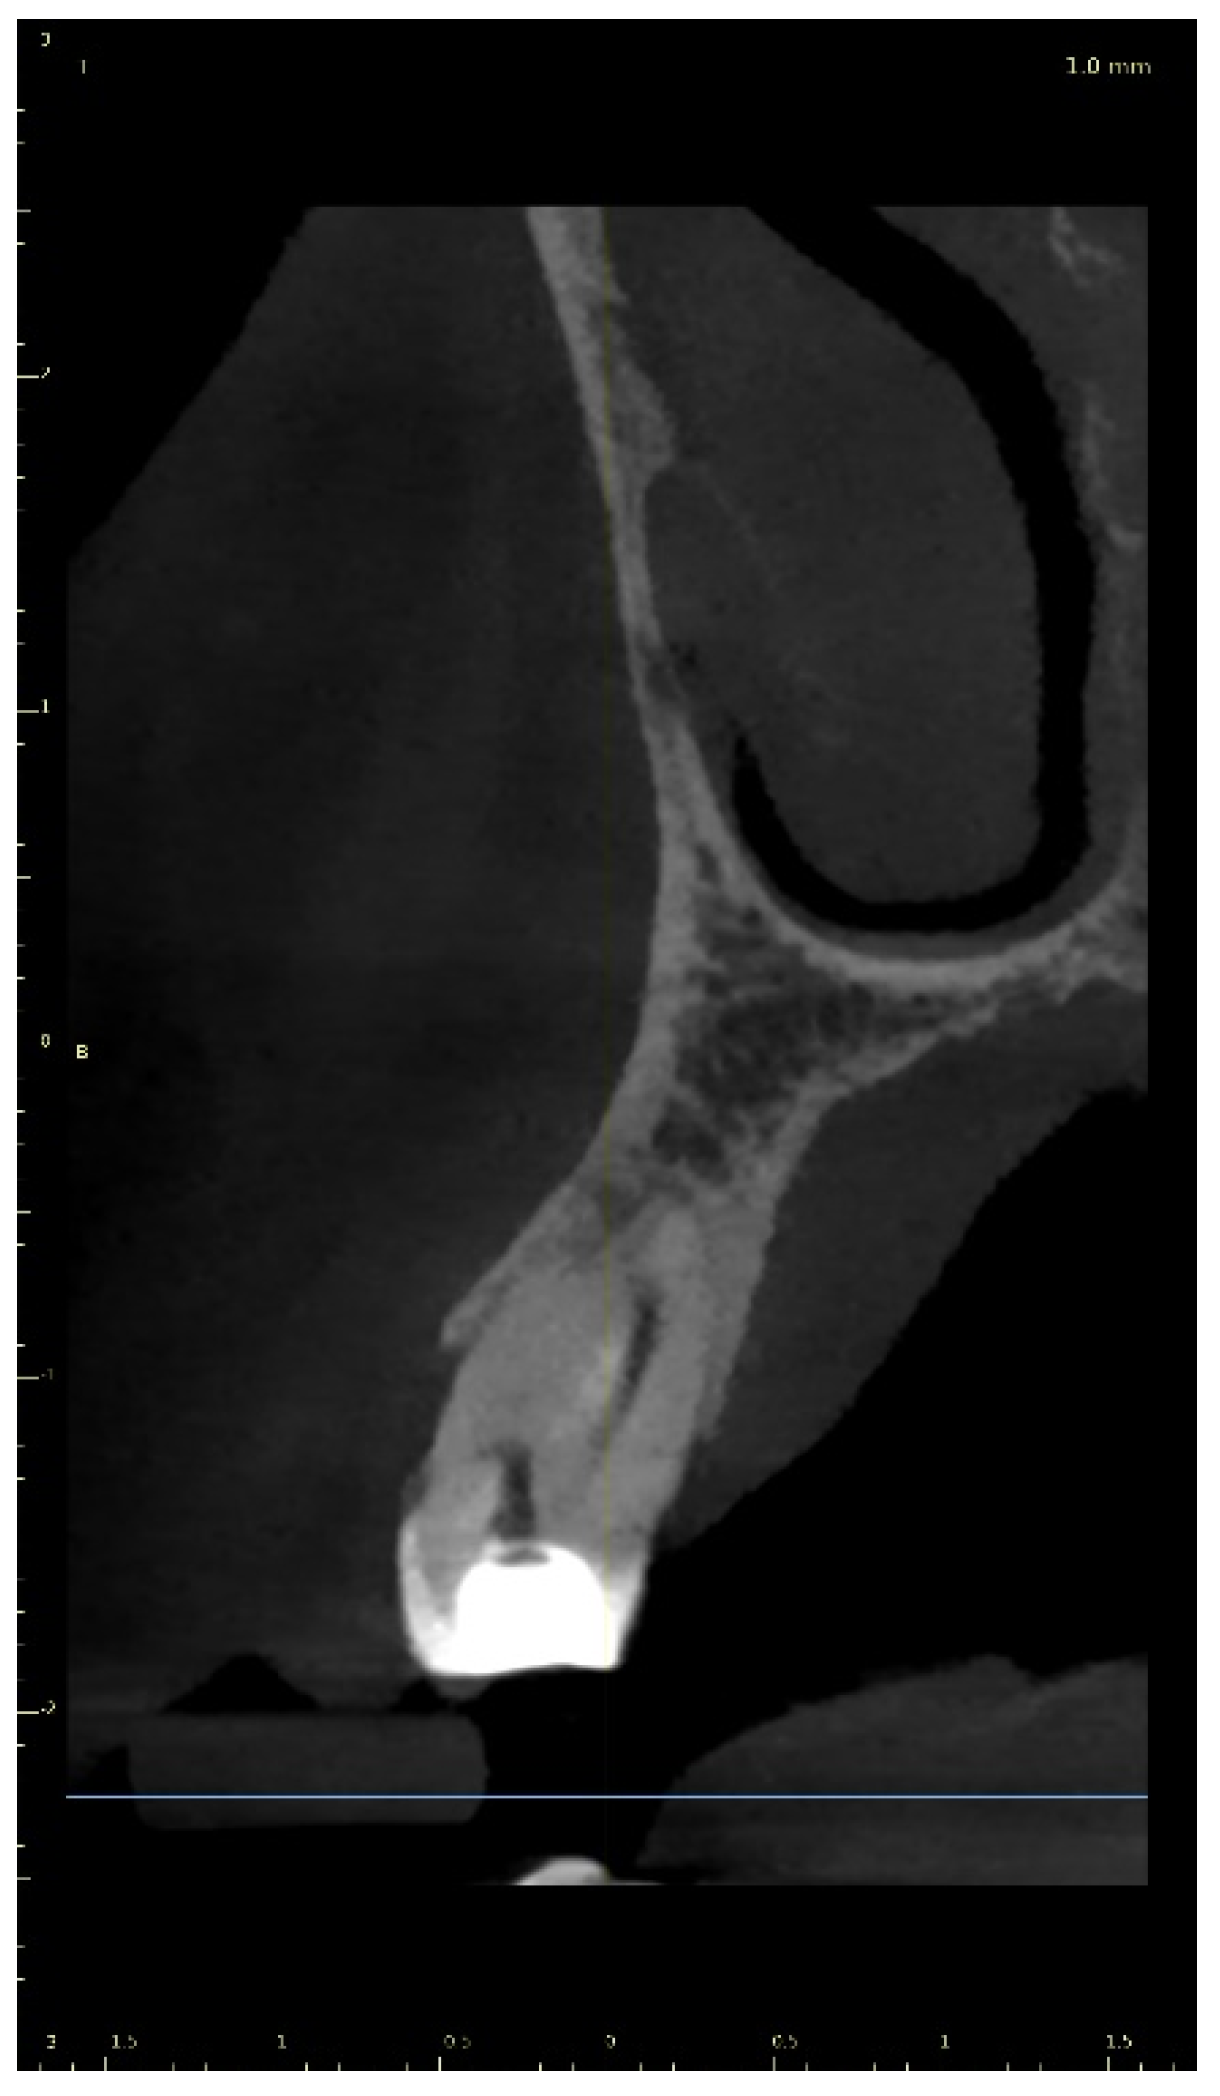

2.2.2. Case Report—Patient D: Symptomatic Pulp Necrosis with Pulp Canal Obliteration

A 68-year-old female patient reported to the endodontic specialist complaining of acute pain upon percussion of her maxillary first premolar (tooth 24), experienced for several days. The patient was healthy and did not have any general or chronic diseases. The clinical examination revealed tenderness to percussion and a negative response to the pulp sensibility test (cold test). Radiographic images revealed pulp canal calcification and the absence of the canal light (Figure 24). A CBCT scan was performed (CS 8100 3D, Carestream, 50 × 50 mm) and confirmed canal calcification (Figure 25). The palatal canal was found during the first visit. The buccal canal was obliterated. Due to the possible risk of higher tooth substance loss and perforation during endodontic access, we decided to perform the endodontic treatment with guided access.

Figure 25. The CBCT image confirmed the calcification of the buccal canal.